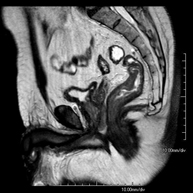

Prueba diagnóstica no invasiva que consiste en la obtención de imágenes de alta definición anatómica de la pelvis mediante el empleo de un campo electromagnético y ondas de radio (con un emisor y un receptor). No utiliza radiación ionizante. Se realiza para estudiar patologías del útero, del ovario, de las trompas y la vagina, ya sean de origen tumoral, inflamatorio o vasculares. Además permite valorar les estructuras adyacentes localizadas en la pelvis, identificando sus alteraciones. A veces requiere el uso de contraste intravenoso (Gadolinio) para caracterizar las lesiones. - RM Pelvis masculina